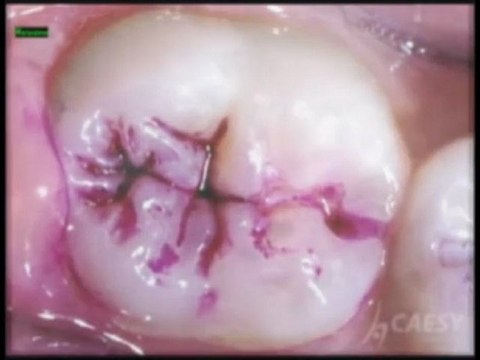

Dr. Sahabi Dentist Glendale has a Family Dental Care practice specializing in Cosmetic Dentistry and Dental care. Call 1-800-734-7454 or visit CaDentalGroup.com